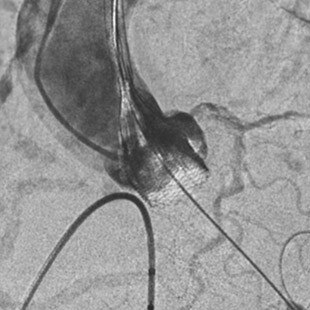

- Paravalvular Leak After Transcatheter Aortic Valve Replacement. The New Achilles’ Heel? A Comprehensive Review of the Literature - https://www.ncbi.nlm.nih.gov/pubmed/23375925

- Aortic regurgitation after transcatheter aortic valve implantation: mechanisms and implications. http://cdt.amegroups.com/article/view/1552/2256

- 5-year outcomes of transcatheter aortic valve replacement or surgical aortic valve replacement for high surgical risk patients with aortic stenosis (PARTNER 1): a randomised controlled trial - https://www.ncbi.nlm.nih.gov/pubmed/25788234